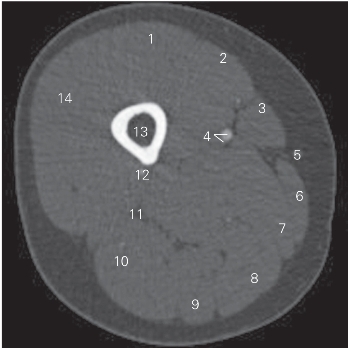

图5-10 经股骨中份的横断层CT图像(骨窗)

1 股直肌 rectus femoris 2 股内侧肌 vastus medialis

3 缝匠肌 sartorius 4 股动、静脉 femoral artery and vein

5 大隐静脉 greater saphenous vein

6 股薄肌 gracilis 7 大收肌 adductor magnus

8 半膜肌 semimembranosus 9 半腱肌 semitendinosus

10 股二头肌长头 long head of biceps femoris

11 坐骨神经 sciatic nerve 12 股深动脉 deep femoral artery

13 股骨 femur 14 股外侧肌 vastus lateralis